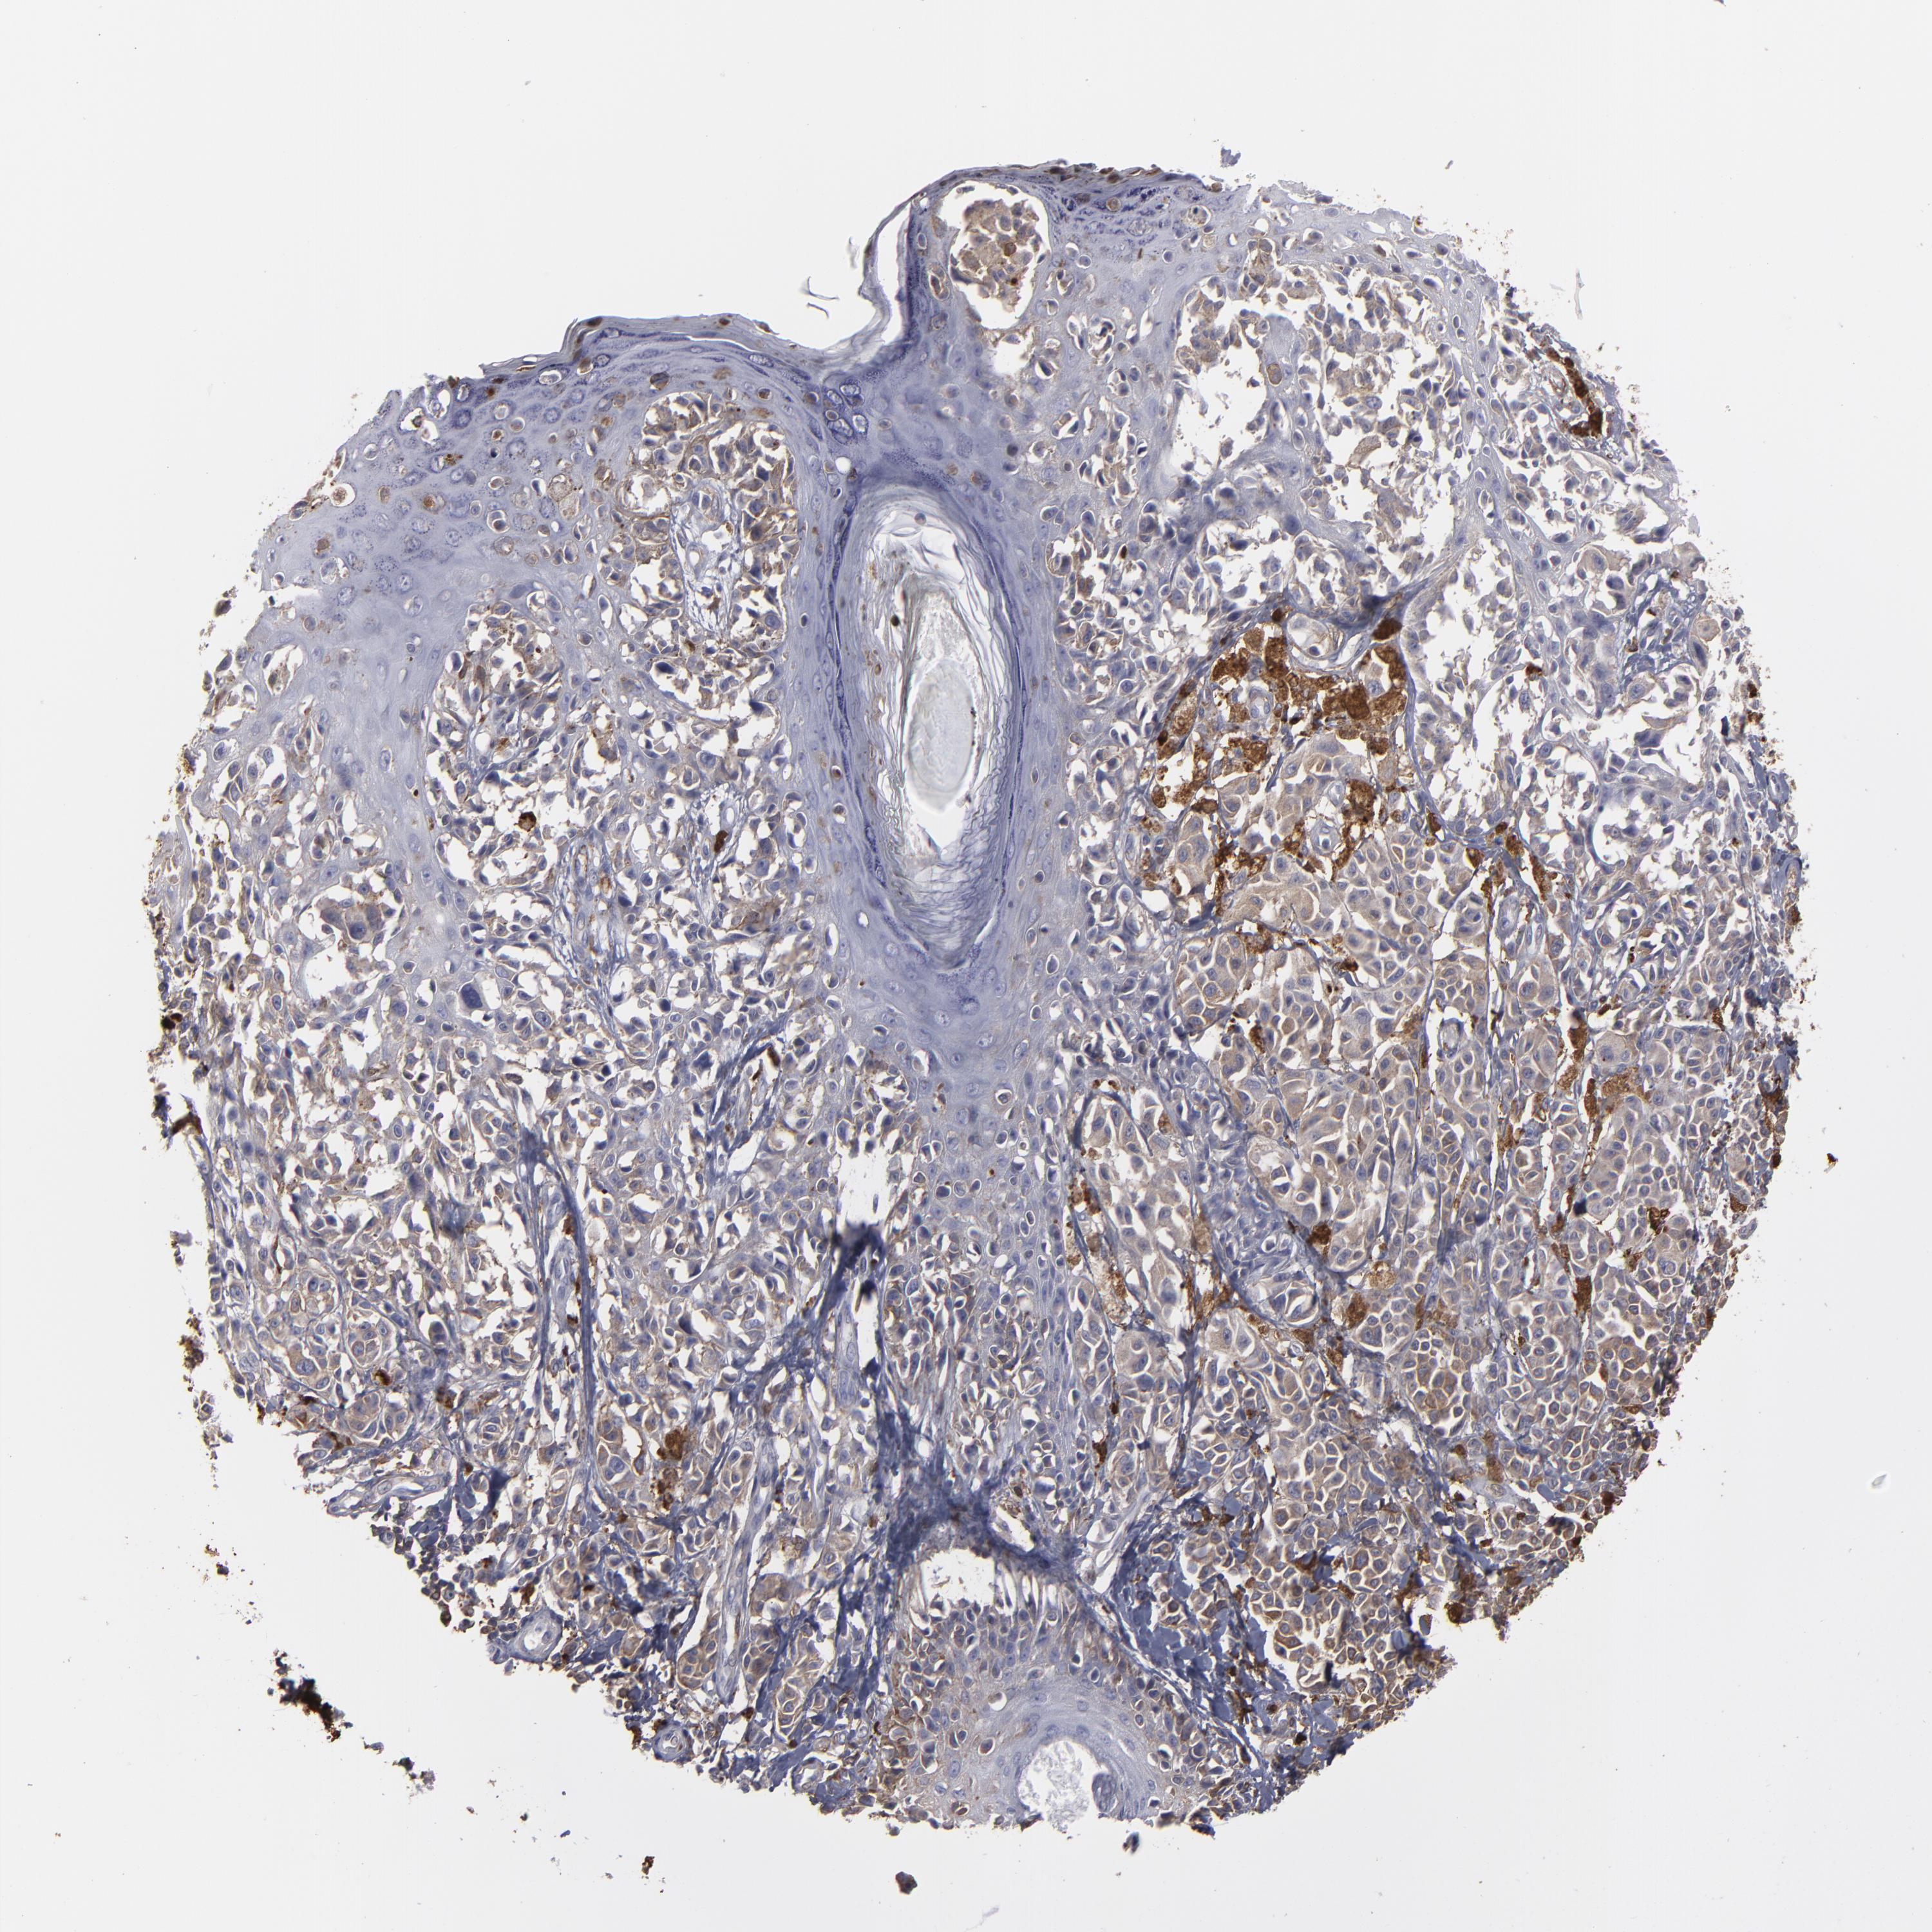

MELANOMA - Protein expressioni

A mouse-over function shows sample information and annotation data. Click on an image to view it in a full screen mode. Samples can be filtered based on level of antibody staining by selecting one or several of the following categories: high, medium, low and not detected. The assay and annotation is described here.

Note that samples used for immunohistochemistry by the Human Protein Atlas do not correspond to samples in the TCGA dataset.

Antibody stainingi

Antibody staining in the annotated cell types in the current human tissue is reported as not detected, low, medium, or high, based on conventional immunohistochemistry profiling in selected tissues. This score is based on the combination of the staining intensity and fraction of stained cells.

Each image is clickable and will lead to virtual microscopy that enables deeper exploration of all samples and also displays staining intensity scores, fraction scores and subcellular localization as well as patient and tissue information for each sample.

Antibody HPA001536

Antibody CAB035996

Staining

High

Medium

Low

Not detected

Intensity

Strong

Moderate

Weak

Negative

Quantity

>75%

75%-25%

<25%

None

Location

Nuclear

Cytoplasmic/membranous

Cytoplasmic/membranous,nuclear

Malignant melanoma, NOS

Malignant melanoma, Metastatic site